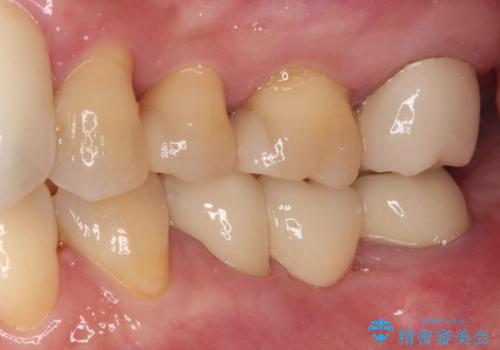

- 前歯の歯肉の腫れを気にして来院された患者様です。

前歯のみならず、奥歯の銀歯や下顎前歯のデコボコなど、色々と気になる部分を治したいとのことでした。

前歯は抜歯が必要であったので、抜歯を行い、その後歯肉移植をおこなった上でオールセラミックブリッジによる補綴治療を行うこととしました。

下顎と上顎臼歯部については矯正治療を行い、奥歯の欠損部位はオールセラミックブリッジを、その他の銀歯はセラミックインレーなどにより治療を行うこととしました。